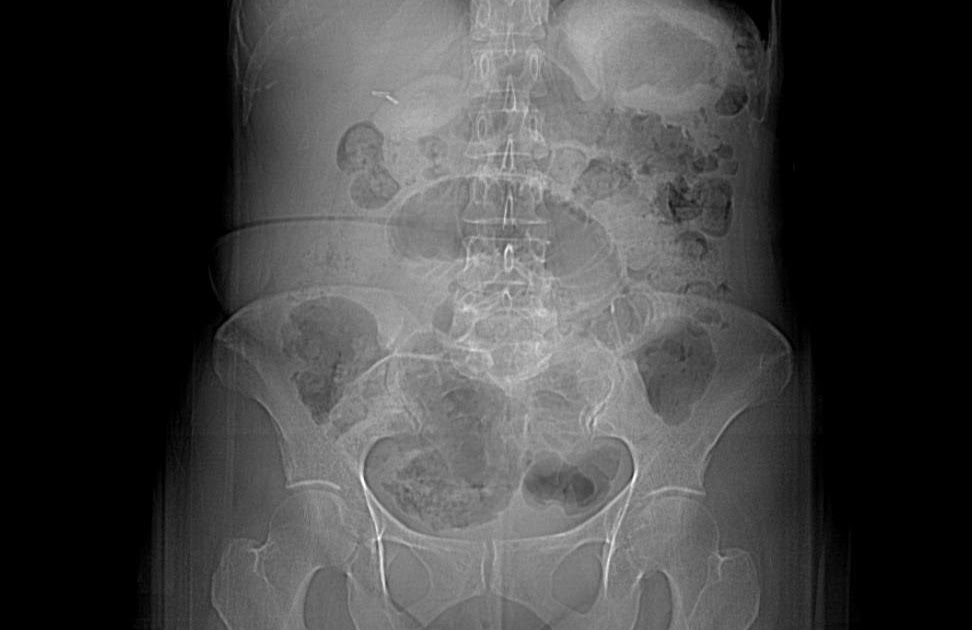

Xray of abdomen demonstrating partial small bowel obstruction. A Closed Loop Obstruction X Ray Usually this is due to adhesions, a twist. A closed loop obstruction is a specific type of bowel obstruction in which two points along the course of a bowel are obstructed, usually but not always with the transition points. In closed loop obstruction, the small bowel is obstructed at two points along its course, thus forming a closed loop. Closed. Closed Loop Obstruction X Ray.

Plain abdominal Xray showing an obstruction and dilated intestinal Closed Loop Obstruction X Ray In closed loop obstruction, the small bowel is obstructed at two points along its course, thus forming a closed loop. Usually this is due to adhesions, a twist. Identifying closed loop small bowel obstruction from adhesions, hernia or volvulus A closed loop obstruction is a specific type of bowel obstruction in which two points along the course of a bowel. Closed Loop Obstruction X Ray.

Plain abdominal xray showed a single loop of dilated small bowel... Closed Loop Obstruction X Ray In closed loop obstruction, the small bowel is obstructed at two points along its course, thus forming a closed loop. No pneumoperitoneum or portomesenteric gas. A closed loop obstruction is a specific type of bowel obstruction in which two points along the course of a bowel are obstructed, usually but not always with the transition points. Usually this is due. Closed Loop Obstruction X Ray.